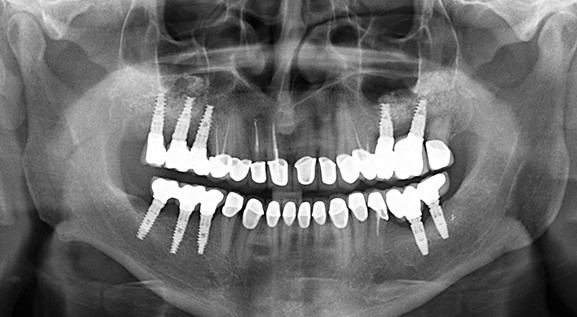

به دلیل آناتومی استخوان‌بندی، مقدار استخوان فک بالا و استخوان فک پایین با یکدیگر متفاوت اس...

جراحی سینوس برای کاشت ایمپلنت دندان